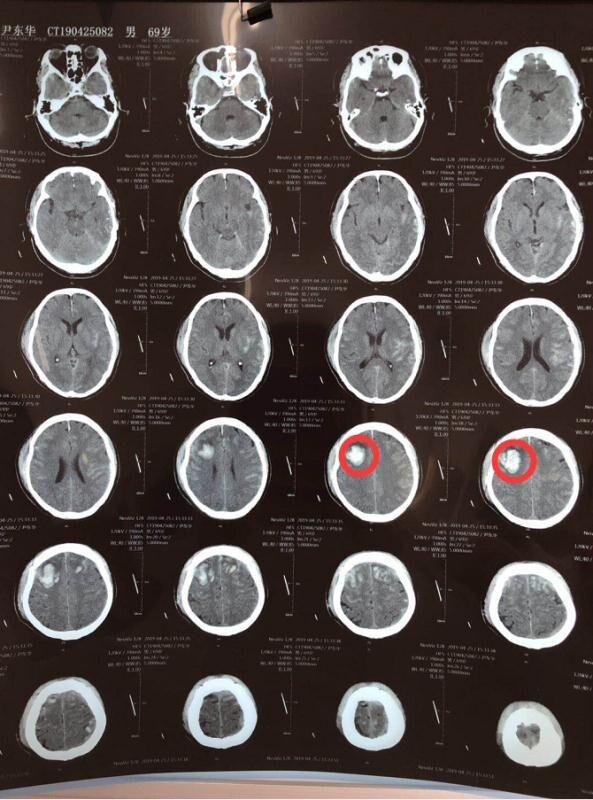

事发当日上午10点20分左右,68岁的王先生在一起车祸中导致重伤,头右颞枕部包块,多处肋骨骨折,被紧急送至沈阳医学院附属第二医院和平院区急诊科,此时距车祸发生已过去2小时,到院时王先生已出现神志恍惚、源于模糊不清等症状,立即开通创伤急诊救治绿色通道,神经外科张沛光主治医师迅速做出判断,紧急为其急行头、胸部等CT检查,检查结果提示颅内出血进行性增加,神经外科孙冬弢主任会诊后,明确诊断为重型闭合性颅脑损伤;弥漫性轴索损伤;双侧硬膜下血肿;双侧额叶、左顶叶、左颞叶、脑干多发脑挫裂伤;外伤性蛛网膜下腔出血;双侧额颞顶骨骨折;肋骨骨折;肺挫伤;低血容量休克;胸腔积液等。随着时间一分一秒的过去,患者已处于深度昏迷状态!患者病情危重,随时有生命危险,需立即手术治疗!

头部CT术前

头部CT术后

于是,在孙主任主持下,联合急诊科、神经外科、普外肿瘤科、骨外科、心胸外科、CT室、超声科等多学科开展了紧急救治,一切准备就绪后,晚20:30分为患者行左额颞及右额扩大冠切开颅,右额叶脑内血肿清除术,双侧硬膜下血肿清除术,右额去骨瓣减压术,术后针对患者出现低血容量休克,普外科、心胸外科、骨科及超声科会诊,明确低血容量原因,为患者输血1000ML。经医护人员一夜的通力合作,患者最终生命体征平稳,术后安返ICU病房。